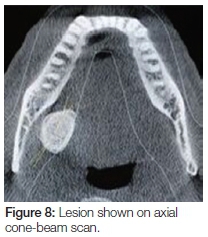

Panoramic, lateral oblique and cone-beam radiographs were taken, all of which revealed a large radiopaque lesion apical to the 48. This confirmed the presence of a sialolith (Figures 6, 7, 8, 9).

The lesion on cone-beam was seen to measure 25 x 26 mm in diameter (Figure 10). This, according to modern literature, would be considered a giant sialolith.